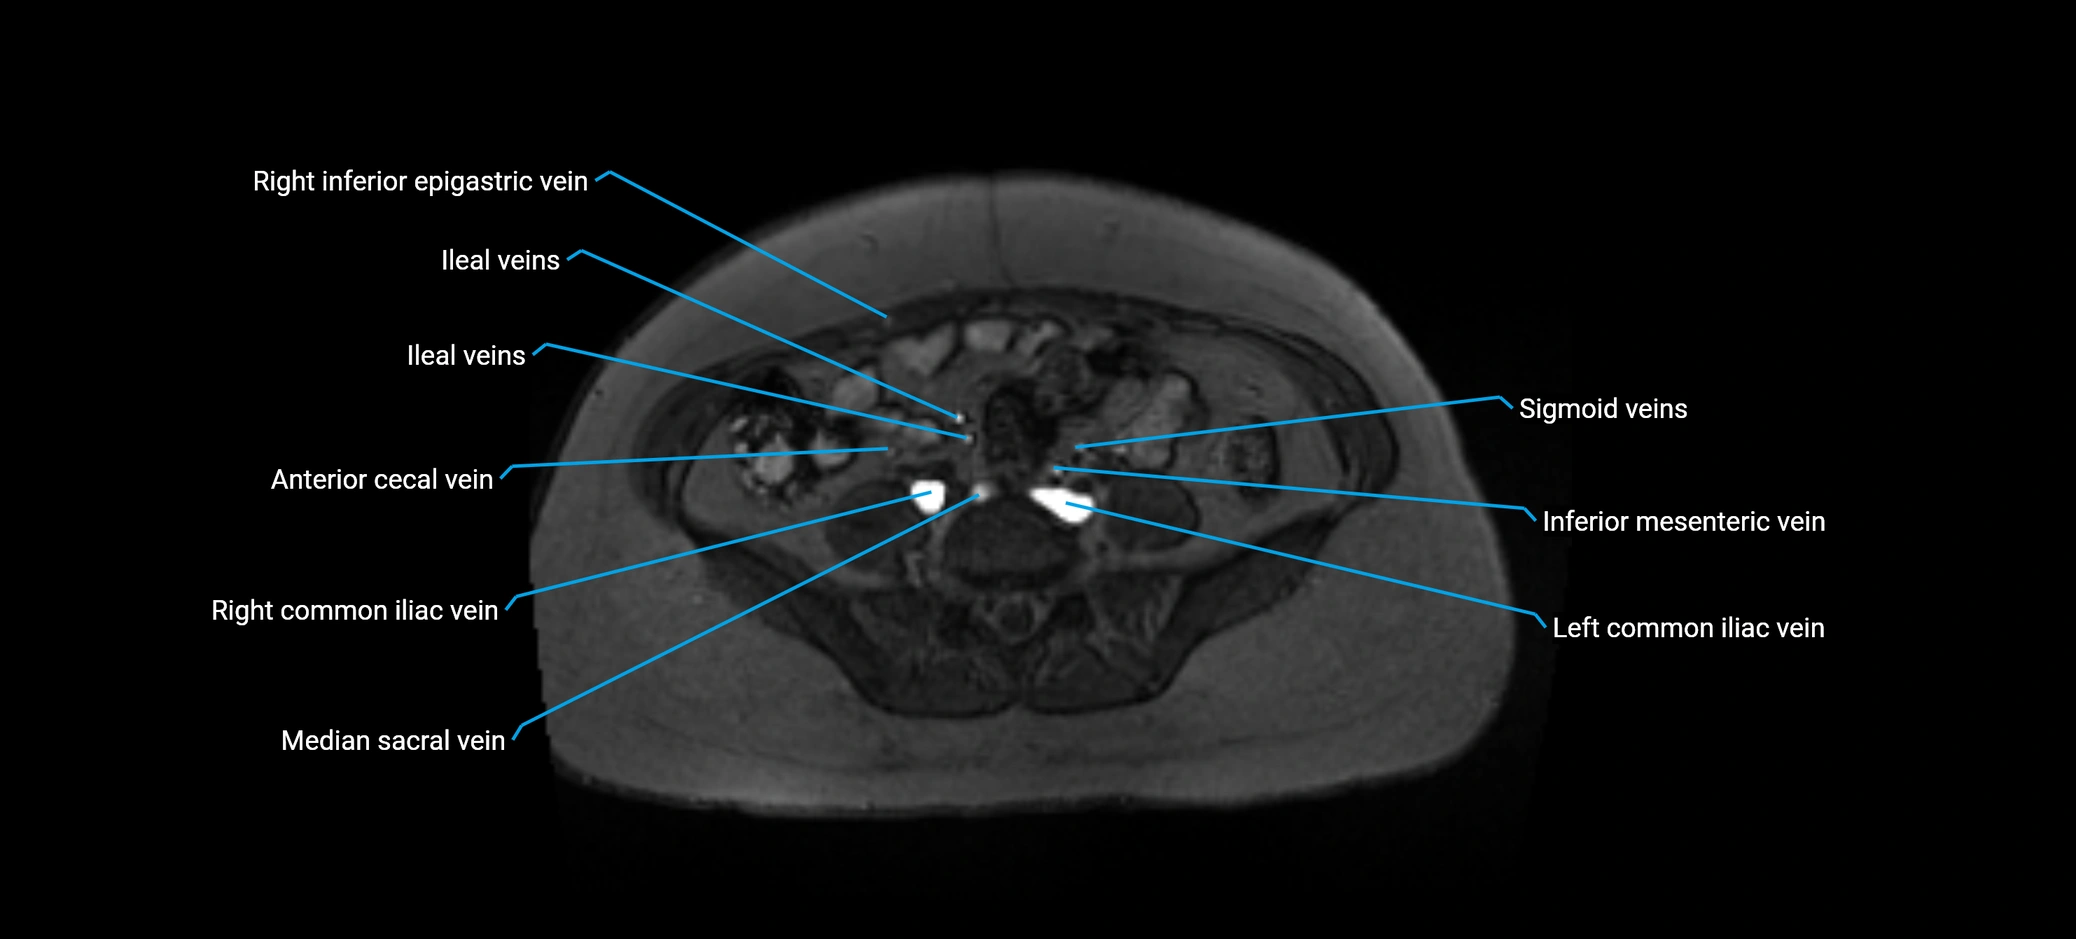

MRI image

image